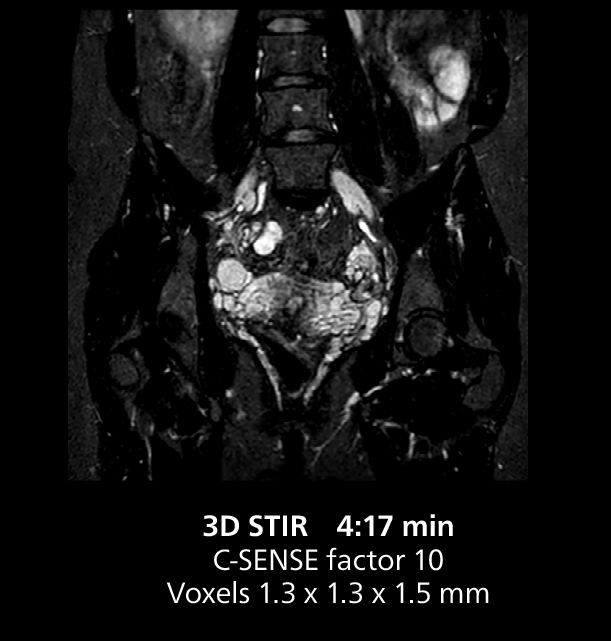

Free-breathing scans provide reproducibility and patient comfort

Dr. Gellée highlights the robust free-breathing scans as “the feature that makes the biggest difference in my daily work. The 3D free breathing sequences are very reproducible, and the axial acquisition is very good. For example, in endometriosis, which is one of my focus areas, it provides high contrast and good resolution so that I can see small details. We also use free breathing for liver and pancreas imaging. In multi-phase liver studies, 4D Free Breathing delivers 3-second temporal resolution, making a dynamic scan with more than one arterial phase possible.”

For elderly patients in particular, free-breathing protocols make exams more comfortable while providing the image quality needed for confident diagnosis. “We have a large elderly population in the city, and because long breath holds are difficult for many older patients, free-breathing is a significant advantage,” Dr. Gellée says. “In cardiac MR for example, with 4D flow and late enhancement, we get excellent diagnostic quality without asking our patients to hold their breath.”

She also uses free breathing with 3D mDIXON to obtain in-phase, water and fat images in a single scan. “It is very reproducible before and after gadolinium, which makes it useful for liver imaging,” she adds.